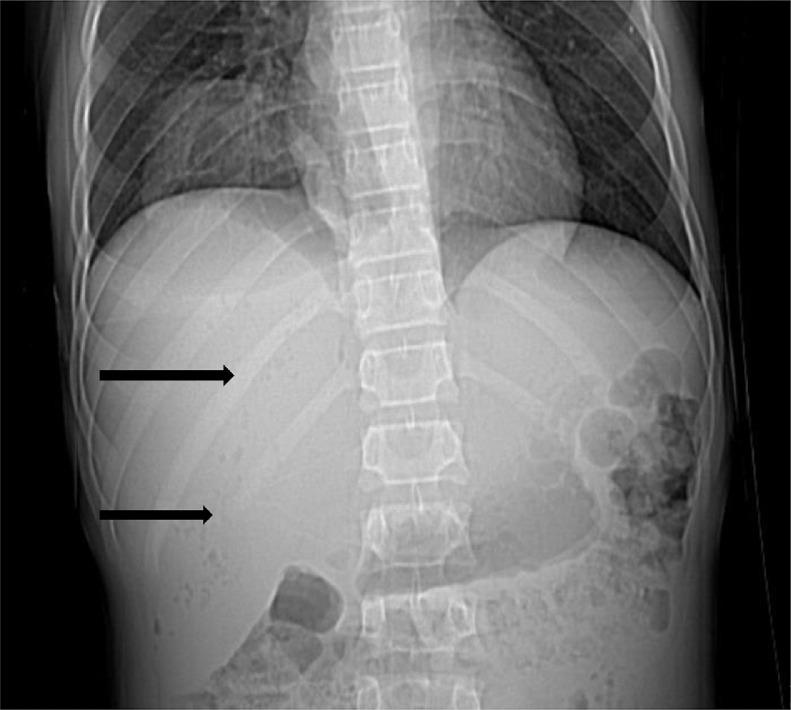

Retrocecal appendicitis usually presents with atypical signs and symptoms which may lead to delayed diagnosis, perforation and serious complications. Development of a large lung abscess secondary to perforation of retrocecal appendicitis in an adolescent patient is an extremely rare entity and to the best of our knowledge has not been described in literature. We present a 15-year-old boy with complaint of chest pain, cough, fever, vague abdominal pain and raised inflammatory markers who underwent CT examination. On CT, a collection with focal calcification was noted in the right iliac fossa that extended along the right retroperitoneum through the retrocrural space in the right lung base communicating with a cavitary pulmonary lesion with air-fluid level. A diagnosis of perforated retrocecal appendicitis with retroperitoneal and right lung abscesses was made. The patient underwent appendectomy and the entire retroperitoneal and lung abscesses were drained. A lung abscess as a complication of perforated retrocecal appendicitis should be in consideration in septic patients with thoracoabdominal infectious manifestations.